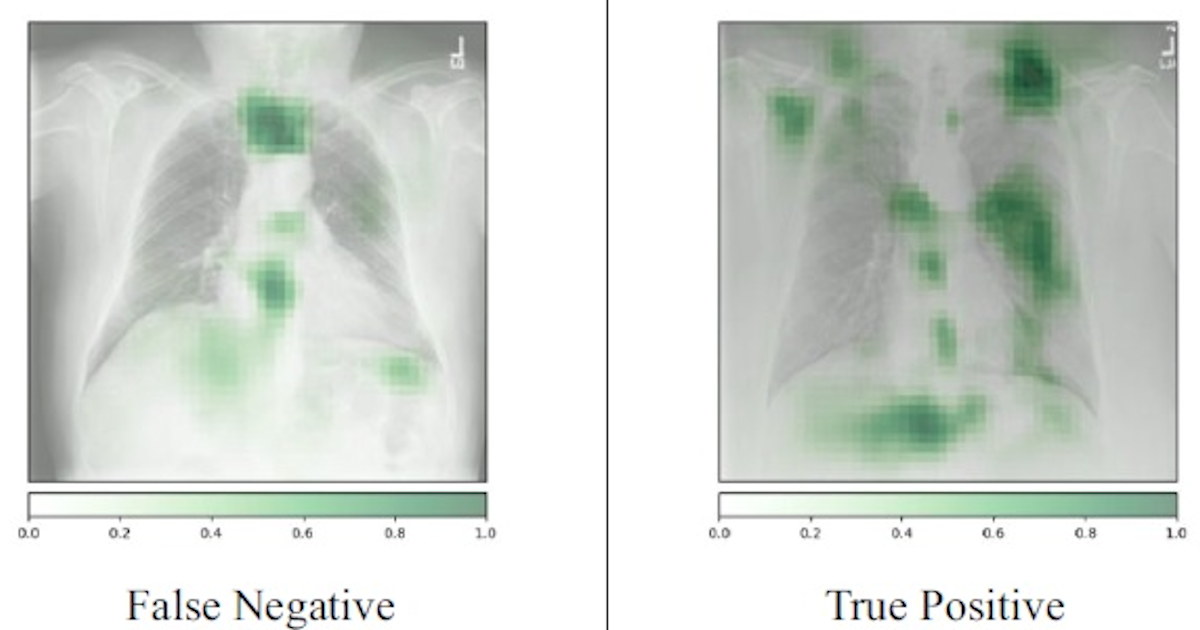

AI reduces false-negative rates on screening digital breast tomosynthesis (DBT) exams, according to new research. buff.ly/DO4XFsf #radiology #mammography #ImagingAI